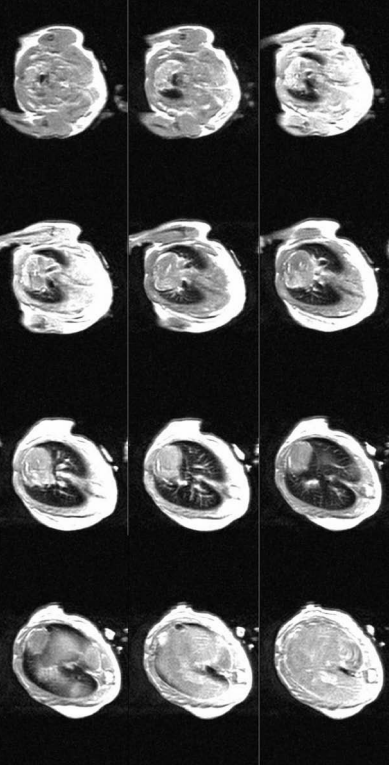

特定感興趣區(qū)域的信號(hào)強(qiáng)度圖像(Ti)(a)在灰度脫粒以去除脈管系統(tǒng)之前和(b)之后,在a中表現(xiàn)為非常高強(qiáng)度的區(qū)域。為了進(jìn)行比較,灰度在a和b之間保持恒定。

基線小鼠肺部12個(gè)軸向切片的信號(hào)強(qiáng)度圖像(針對(duì)無反轉(zhuǎn)準(zhǔn)備脈沖或Ti的特定情況),從氣管向下移動(dòng)到橫膈膜。每幅圖像代表1毫米厚的切片。在這些原始信號(hào)強(qiáng)度圖像中,基線和暴露的小鼠無法區(qū)分。